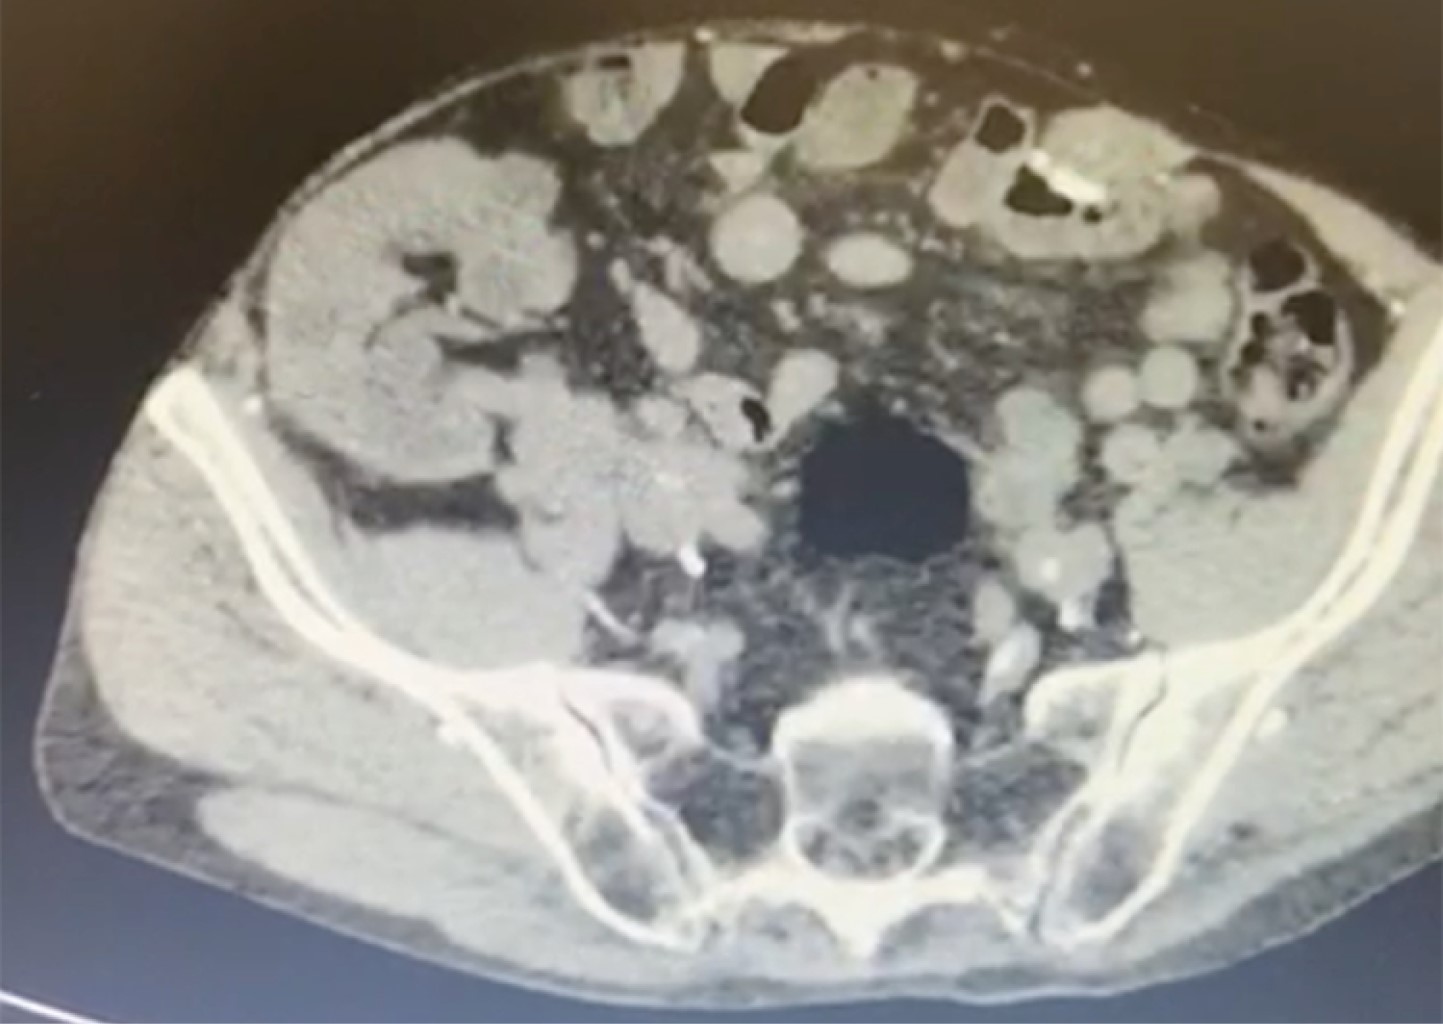

Figure 3